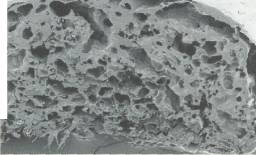

Tabii bu teknolojiyi ideal şekle getirmek çok kolay değil. Karaciğer içinde değişik görevleri olan milyonlarca hücre var. Yalnızca bir gram karaciğer dokusunda yaklaşık 100 milyon karaciğer hücresi bulunuyor. Hücrelerin gerekli noktalara yerleştirilmesi ve buradaki konumlarını korumalarının sağlanması oldukça güç. Yapay karaciğer oluşturulmasında karşılaşılan diğer bir güçlükse, organın mikroplardan arındırılması. Yapay organların içine hiçbir mikrobun girmemesi gerekiyor. Bu nedenle, çalışmalarda kullanılan tüm cihaz ve aletlerin steril, yani mikroptan arındırılmış olmaları çok önemli.

Yapay karaciğer oluşturmak, teknik açıdan oldukça güç. Poliüretan köpük iskelet kullanan bilim adamları yapay karaciğer oluşturabiliyorlar. Köpük içine yerleştirilen karaciğer hücreleri, mikrokümeler oluşturuyor. Elde edilen üç boyutlu yapay karaciğer vücut dışında 10 gün süreyle işlev görüyor. Karaciğer yetmezliği olan domuz ve farelere yerleştirilen bu yapay karaciğerler oldukça iyi sonuçlar verdi. Bilim adamları, deney aşamasındaki köpük karaciğerleri daha da geliştirerek, insanlarda kullanımı için çalışıyorlar.